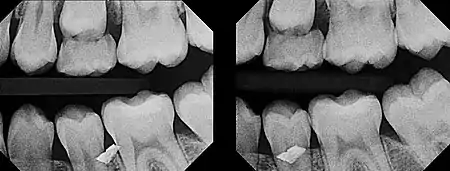

The initial radiograph (left) indicated that a metal foreign object was embedded somewhere in or near the teeth, but upon clinical examination, it could not be found anywhere in the gum tissue. Upon taking another radiograph (right) exposed at a very severe distal angulation, however, the metal fragment appeared to move a great deal to superimpose on the facial aspect of the premolar, indicating that the fragment was way more buccal than initially suspected. With the use of this second film, it was determined that the metal fragment was indeed embedded in the cheek.

The buccal object/SLOB rule is a method used to determine the relative position of two objects in the oral cavity using projectional dental radiography.